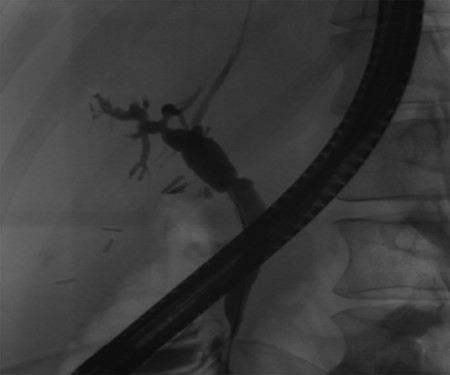

Post-operative ERCP displaying left sided intrahepatic duct biliary dilatation.

A 35-year-old female with a medical history significant for acute biliary pancreatitis status post laparoscopic cholecystectomy, presented to the surgery clinic as a new consult for a large cystic liver mass with increasing abdominal pain for 2 weeks. Patient reported suffering from severe pain in right chest, shoulder and diffuse abdominally that worsened with standing. Patient complained of inability to inspire due to pain and a 10-pound weight gain over 2 months. She confirmed decreased appetite especially with solids, nausea and emesis, alternating constipation and diarrhea, bruising, and pruritus at night. Computed tomography (CT) scan demonstrated a peripherally septated 10 x 7 cm cystic mass in the liver with intrahepatic biliary dilation (Fig. 1). The patient was referred for endoscopic retrograde cholangiopancreatography (ERCP) to establish preoperative biliary anatomy and was found to have moderate compression of the common hepatic duct managed with a right hepatic biliary endoprosthesis (Fig. 2); no obvious communication of the biliary tree with the cystic lesion was seen. Patient symptoms persisted despite optimizing with a protein-rich liquid diet; thus, the decision was made to proceed with the surgical plan for an open partial central hepatectomy. The patient was taken to the operative theater. After induction of general anesthetic, an upper midline incision was made. Inspection of the abdomen and liver showed no metastatic lesions grossly or with ultrasonographic imaging. The cyst was visible upon entry into the abdomen with no solid component to the mass in proximity to the cystic neoplasm. The second portion of the duodenum was adherent to the cyst with inflammatory adhesions and was quite boggy. A partial central hepatectomy was performed; a 3 mm biliary duct was found communicating to the cyst only with no drainage to the minimal liver parenchyma that was removed (Fig. 3). The cyst was resected en-bloc and was sent for permanent section (Fig. 4), which diagnosed the tumor as a low-grade mucinous cystic neoplasm measuring 8.5 × 7.2 × 6.4 cm. Microscopy revealed a smooth-walled, multiloculated cyst filled with a yellow-golden, semi-transparent and mucinous fluid (Fig. 5a–c). The cyst was lined by a mucinous epithelium with ovarian-type stroma. No high-grade dysplasia or malignancy was identified. The postoperative course was uneventful, and the patient was discharged on postoperative day 6. At the 4-week postoperative visit, the patient was healing well with some incisional soreness; patient was seen for removal of her biliary endoprosthesis, and ERCP found left sided intrahepatic duct biliary dilatation including a small biliary fistula from the left system (Fig. 6) with the appearance of torque on the extrahepatic biliary tree. A biliary endoprosthesis was left in place, and the patient returned for repeat ERCP 4 weeks later with resolution of all findings (Fig. 7). At present, patient remains alive with no signs of recurrence.